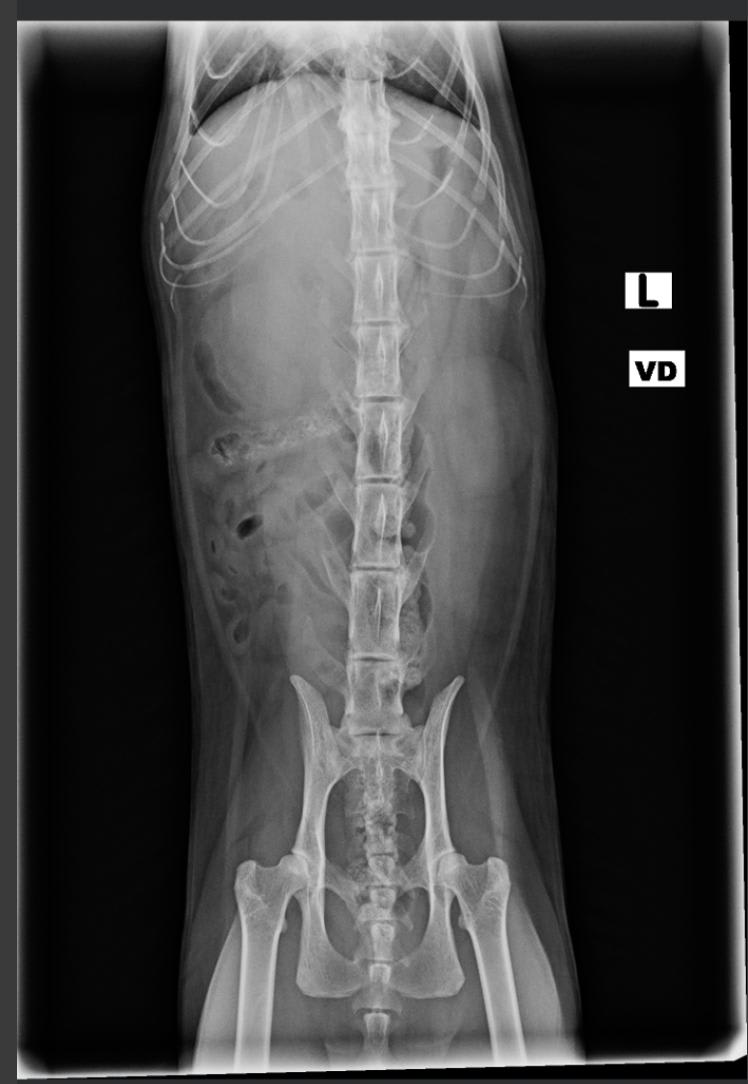

Pet's info: Cat | American Shorthair | Male | neutered | 6 years and 8 months old | 9 lbs

I took my cat to the vet Friday. The vet thought he had an intestinal adhesion, but called back saying it was inoperable lymphoma. I do not have the ultrasound images. From the x-rays can you identify the mass? Could it be anything else?

So very sorry for you loss of Indy. My condolences. I can see on the x-ray what the vet was thinking may have been an adhesion. I cannot tell you what it is though just by looking at the x-ray. The only way to know what the mass is/was is to have sent it to a laboratory for histopathology. Masses can be any number of things. I can tell you that lymphoma is quite common in cats. Unfortunately, we are not going to be able to help you with this via the internet as we were not there to see what happened. If you wanted a definitive diagnosis then a necropsy (autopsy) would have been needed with tissue samples sent to the lab for analysis.